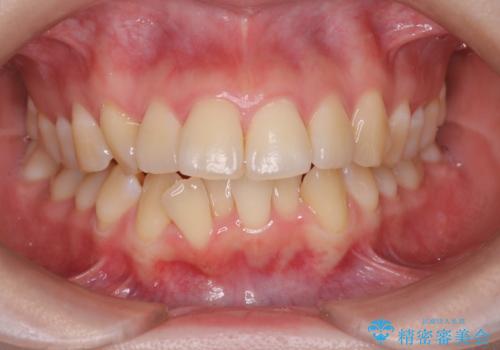

【審美装置】前歯のがたがたを治したい

担当医 河口智英